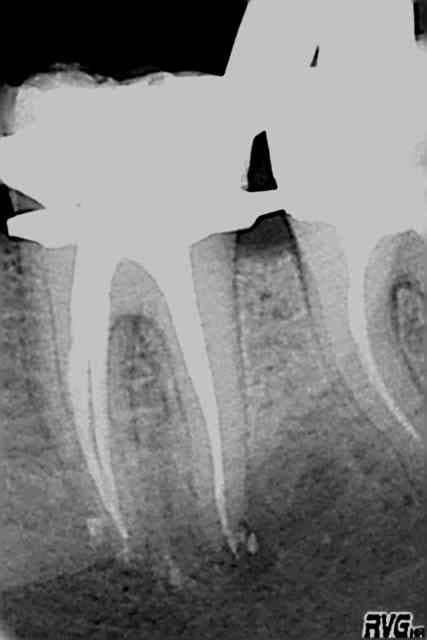

Jolie endo Steph;)